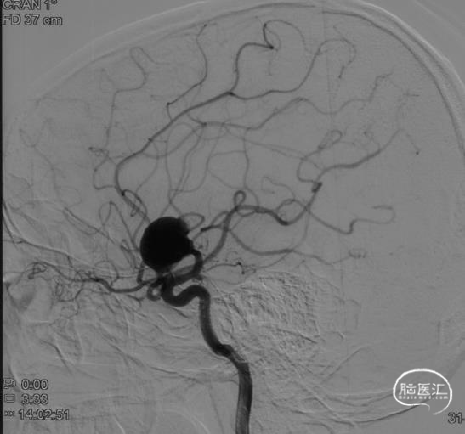

正侧位造影,可见明显喷射征(DSA)

压颈示前交通开放(DSA)

测量动脉瘤大小:18.87×16.06mm;M1段起始段直径:2.97mm,远端2.52mm,下干直径1.99mm(DSA)

选取工作角度(DSA)

术后即刻工作角度造影示动脉瘤内造影剂滞留,豆纹动脉等分支血管通畅